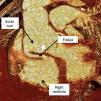

A 68-year-old man with a history of systemic hypertension and chronic renal failure was admitted to our emergency department with chest pain and dyspnea. He had undergone tube graft replacement of the ascending aorta due to an acute type A aortic dissection 10 years previously. On admission he was hypertensive and tachycardic with a continuous murmur at the left upper sternal border. The electrocardiogram revealed nonspecific repolarization abnormalities and the transthoracic echocardiogram showed a severely dilated aortic root with an intimal flap and continuous turbulent flow from the aortic root toward the right ventricle (Figures 1 and 2). There was moderate aortic regurgitation caused by poor leaflet coaptation. The right chambers were slightly dilated and both ventricles had normal systolic function. Chest computed tomography confirmed aortic root dissection with a fistula between the aortic false lumen and right ventricle (Figures 3 and 4). The coronary arteries were not involved. The patient was rejected for surgery due to very high surgical risk and died a few days later after sudden hypotension.